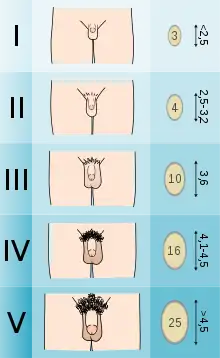

Puberty is considered delayed when the child has not begun puberty when two standard deviations or about 95% of children from similar backgrounds have.[7][8][9]

In North American girls, puberty is considered delayed when breast development has not begun by age 13, when they have not started menstruating by age 16,[3] and when there is no increased growth rate.[8] Furthermore, slowed progression through the Tanner scale or lack of menarche within 3 years of breast development may also be considered delayed puberty.[8]

In the United States, the age of onset of puberty in girls depends on racial background. Delayed puberty means the lack of breast development by age 12.8 years for White girls, and by age 12.4 years for Black girls.[7][8] The lack of menstruation by age 15 in any ethnic background is considered delayed.[8]

In North American boys, puberty is considered delayed when the testes remain less than 2.5 cm in diameter[3] or less than 4 mL in volume by the age of 14.[4] Delayed puberty is more common in males.[3]